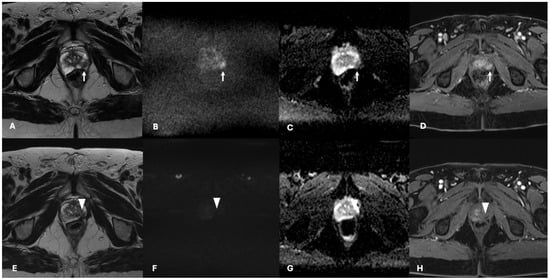

3.3. Oncological Outcomes